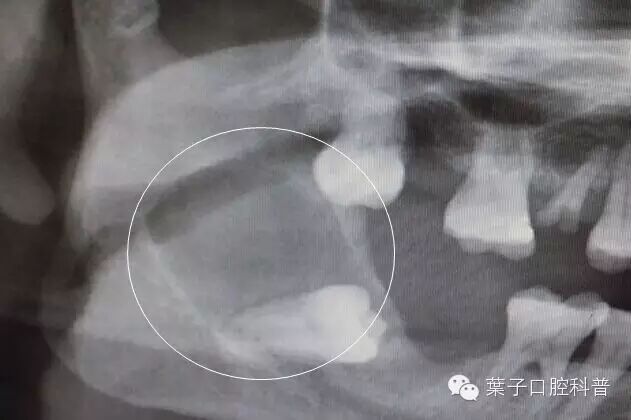

智齿引起下颌骨大面积囊肿